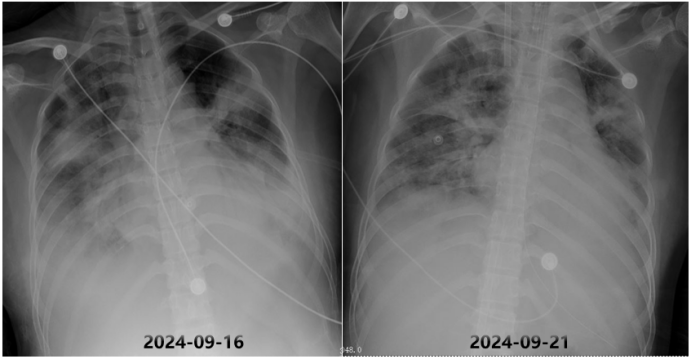

• 床旁胸片:双肺浸润影(图2)

图片

2  患者转入RICU后床旁胸片

9月21日复查床旁胸片,可见双下肺病变较前吸收改善(图6)

6  复查床旁胸片